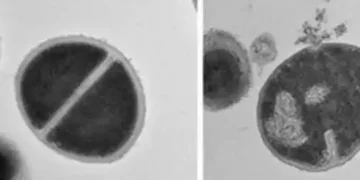

Experiments showed that human cells with active proteasomes effectively controlled bacterial growth, while blocking proteasome activity allowed infections to spread, WIS said.